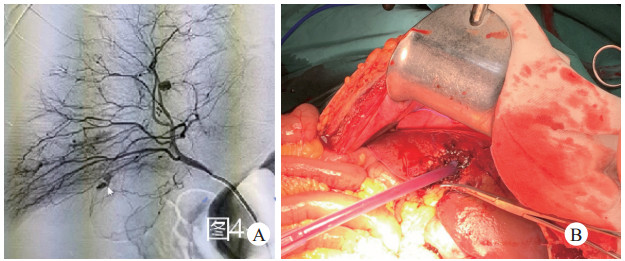

6月18日19时患者肝破裂诊断明确,需立即行手术止血治疗。经控制性液体复苏[6],及血管活性药物应用,患者血压不回升甚至仍持续下降,开腹手术风险极大。按照“创伤损伤控制手术的原则”立即行“局麻下经皮血管造影+介入栓塞”[7]。术中见:肝右动脉多发点状造影剂外溢及假性动脉瘤(图 5A),右侧腹壁下动脉、右侧臀上动脉分支、右侧臀下动脉分支、左侧臀下动脉分支均见点状造影剂外溢,分别使用微导管超选择至上述病变动脉行栓塞治疗。

| 图 5 地震伤员肝脏损伤(右肝第五段) |

初步控制肝脏出血后,于6月18日22时由肝胆外科急诊实施“剖腹探查+肝破裂修补术+腹腔冲洗置管引流术”, 术中见:右肝第五段可见长10 cm,深4 cm不规则裂口,活动性出血明显(图 5B);腹腔内积血及血凝块共约3 500 mL、后腹膜、膀胱周围间隙及盆腔可见血肿;术后返回EICU。术后当天腹腔压力降低至12 cmH2O。恢复肾灌注后,高钾,肾功能较前好转。